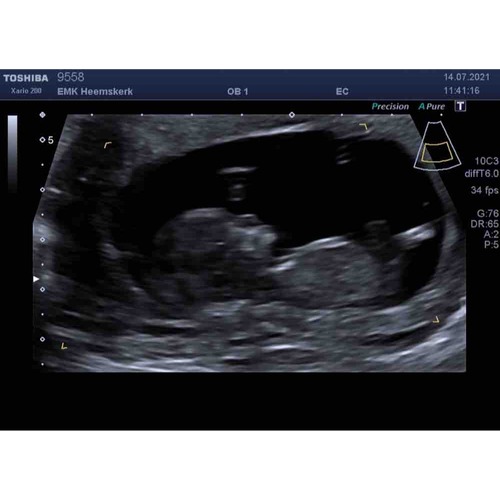

Ik vond dit zo leuk 😍 nu is dit wel iets eerder en iets later, maar dan kan je al wel het verschil zien 😁

Dit is die van ons met 11 weken zo bijzonder